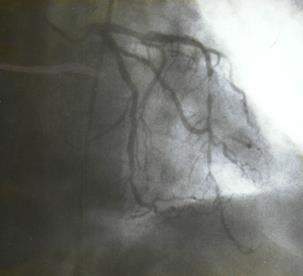

Коронарографическое исследование проводили на ангиографических установках "AngioscopeD" фирмы "Siemens" (Германия), "Integris 3000" фирмы "Philips" (Голландия) по методу М. Judkins и Sones. Для контрастирования КА использовали омнипак 300-350. КГ ЛКА выполняли в стандартных проекциях по методике Gensini: правая косая 150 и 450, левая косая проекция 600, левая боковая 900. В некоторых случаях использовали дополнительные проекции: левая передняя косая 450-750, каудокраниальная 300.КГ ПКА выполняли в стандартных проекциях: правой косой 450, левой косой 600, левой боковой 900 от сагиттальной оси. Анализ коронарограмм осуществляли на просмотровом аппарате "Tagarno 35AX". При анализе коронарограмм определяли тип кровоснабжения сердца, состояние основного ствола ЛКА, степень и уровень поражения коронарных артерий, диаметр коронарных артерий, количество пораженных артерий, наличие коллатерального кровотока.

Коронарография выполнена всем больным. Всем больным выполнена ангиография левой внутренней грудной артерии.